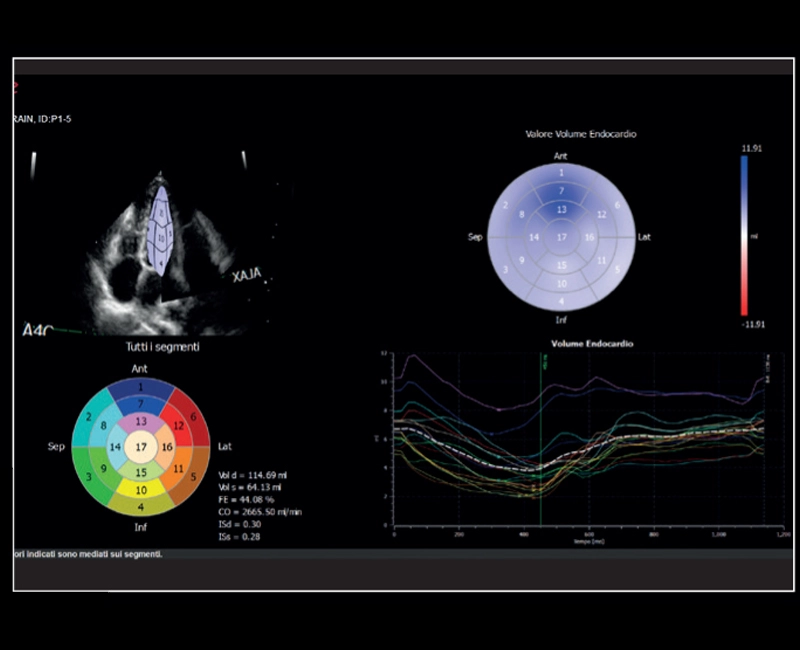

MyLab™E80 - AutoEF

MyLab™E80 - AutoEF

MyLab™Omega eXP - AutoEF

MyLab™Omega eXP - AutoEF

MyLab™X8 Platform - Zero-click EF measurement with Uterus - XLight 3D/4D exploration AutoEF

MyLab™X8 Platform - Zero-click EF measurement with Uterus - XLight 3D/4D exploration AutoEF

MyLab™X90 - AutoEF Automatic Ejection fraction assessment of the left ventricle

MyLab™X90 - AutoEF Automatic Ejection fraction assessment of the left ventricle

MyLab™X5 - AutoEF

MyLab™X5 - AutoEF

MyLab™X6 - AutoEF

MyLab™X6 - AutoEF

MyLab™X7 - AutoEF

MyLab™X7 - AutoEF

MyLab™Omega - Zero-Click AutoEF

MyLab™Omega - Zero-Click AutoEF

MyLab™A50 - AutoEF

MyLab™A50 - AutoEF

MyLab™A70 - AutoEF

MyLab™A70 - AutoEF